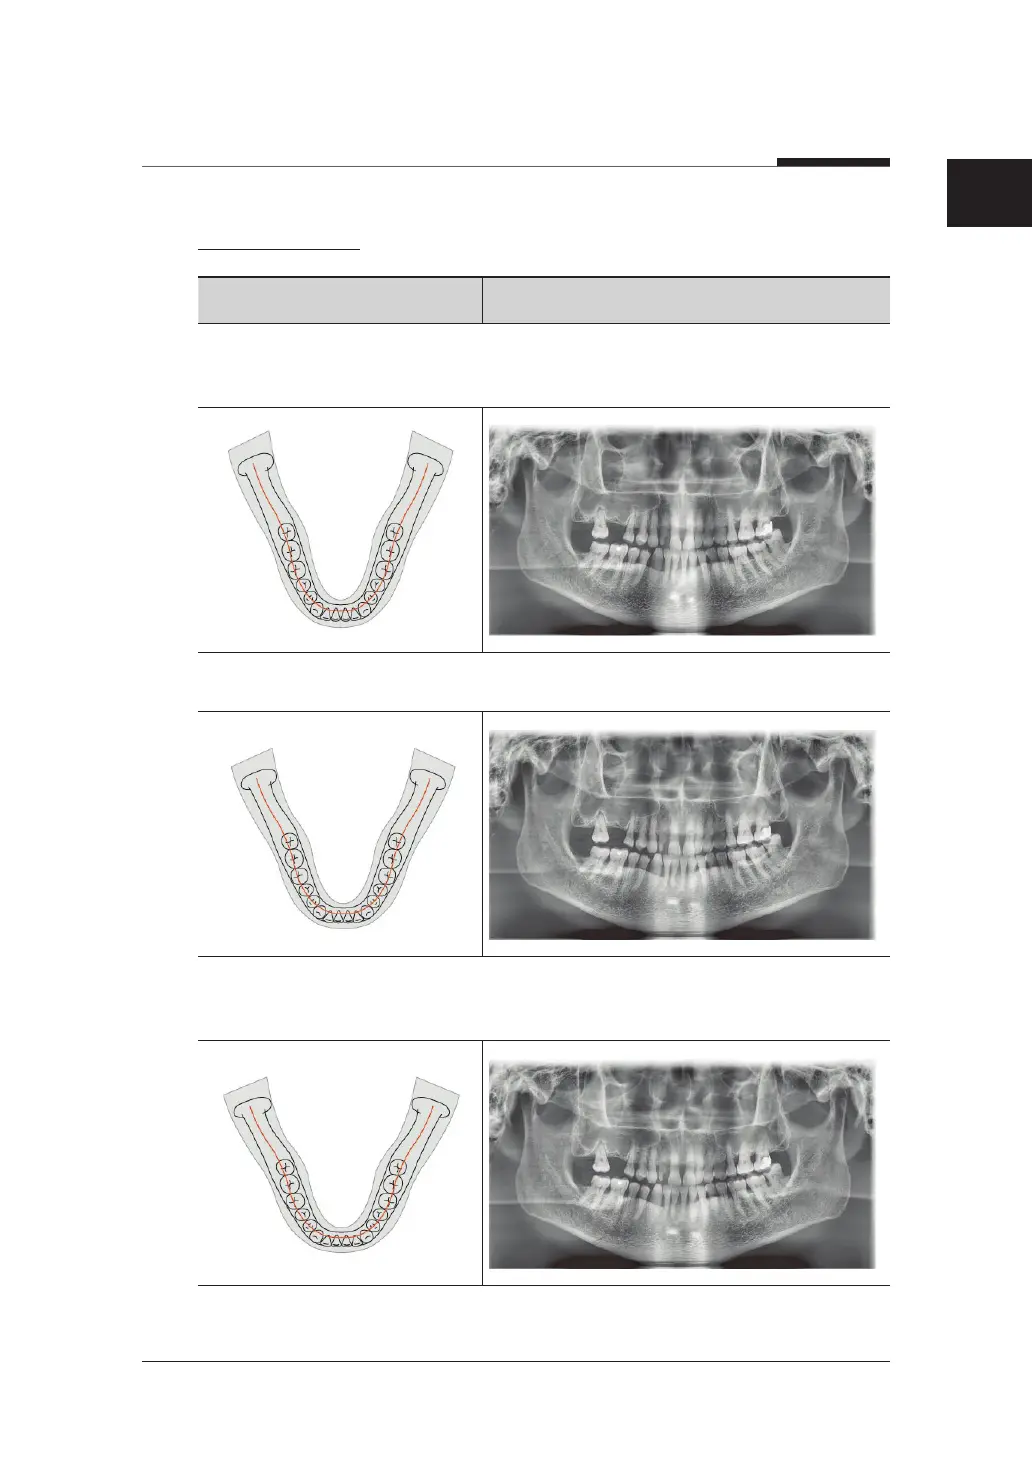

Arch Selection

Examination Program Image

Narrow (Standard): Panoramic image of V-shaped palatal arches (small number of

adult females)

Normal (Standard): Panoramic image of normal adult palatal arches

Wide (Standard): Panoramic image of square-shaped palatal arches (some number of

adult males)